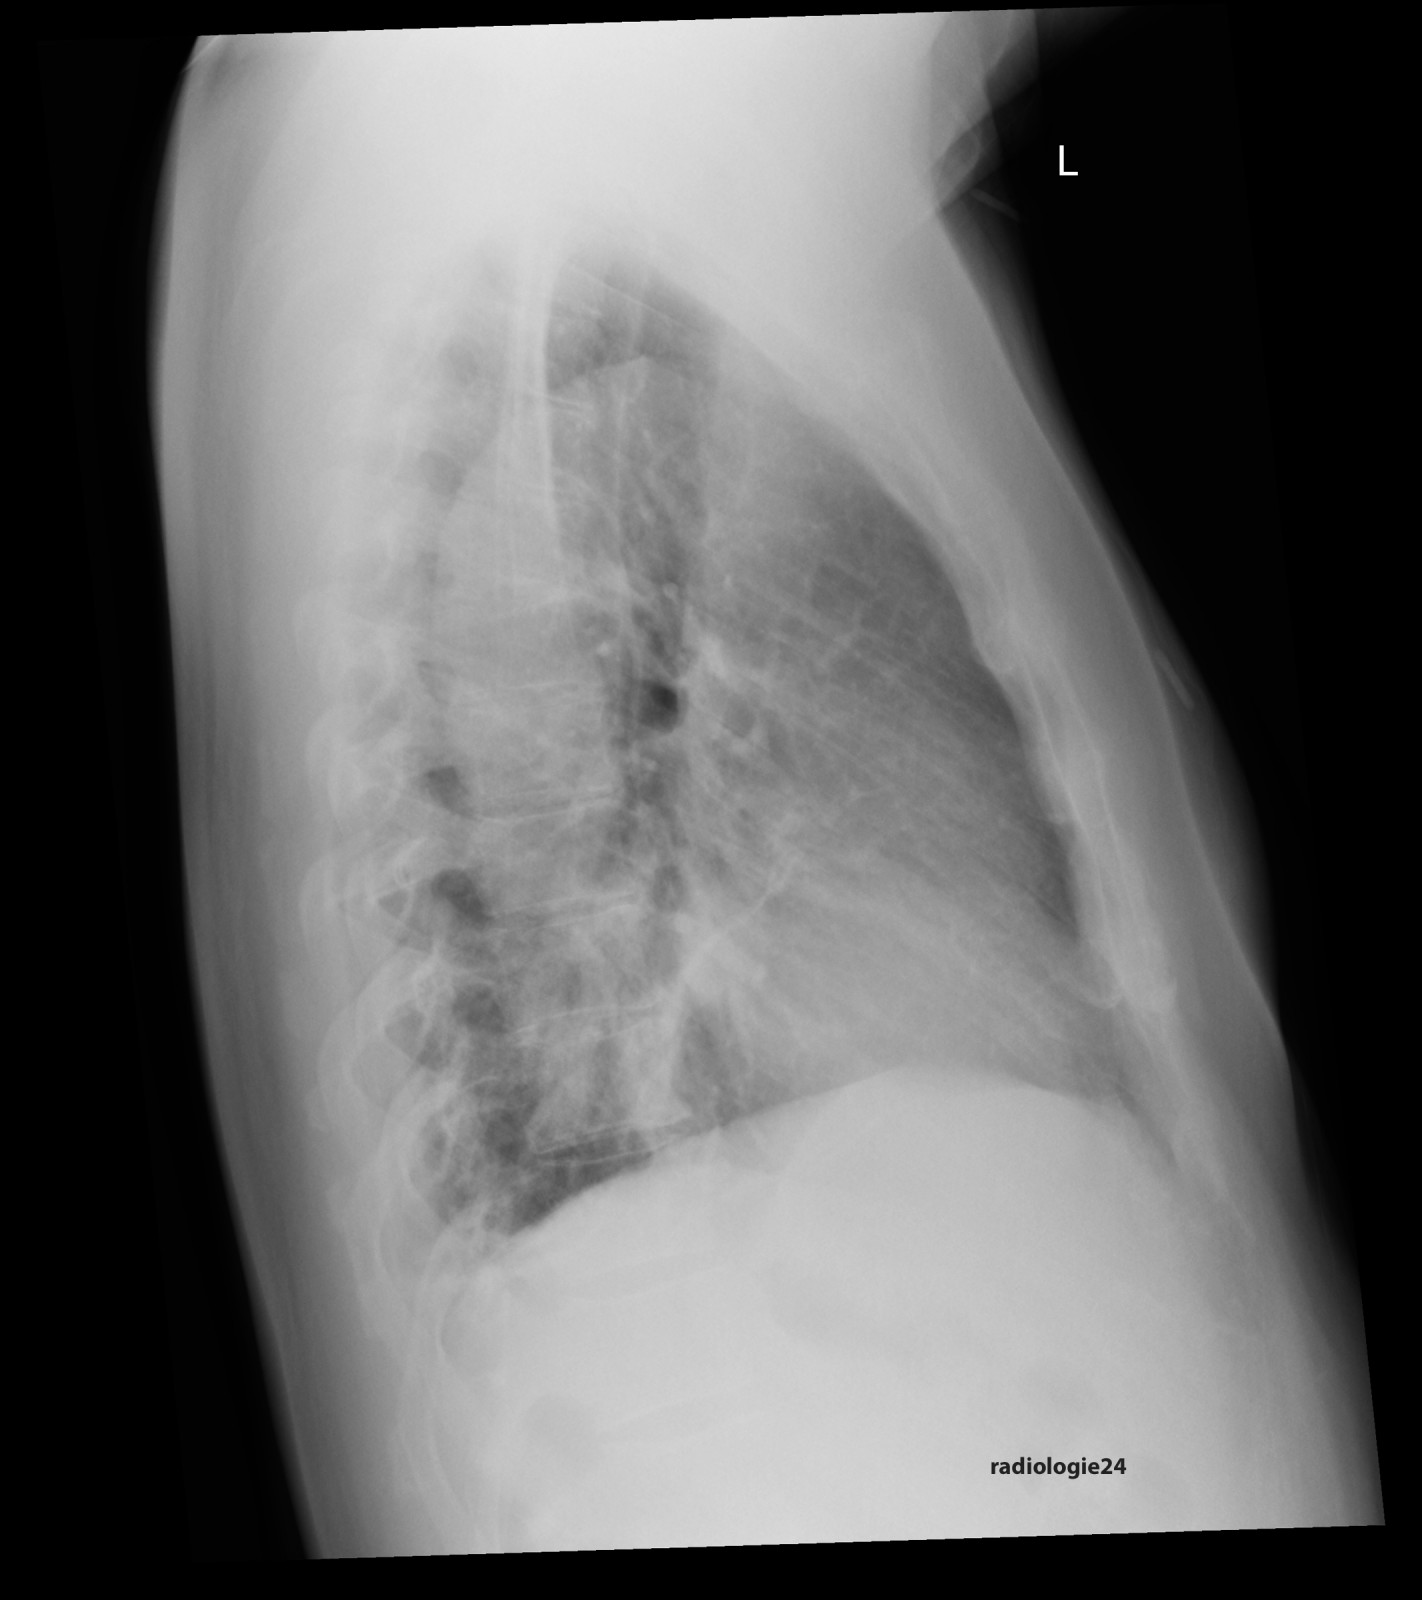

Röntgenfall des Monats Oktober 2017 mit Auflösung

48 jähriger Patient. Klinische Angaben: Thoraxschmerzen, afebril, hypertensiv entgleist. Fragestellung: Infektzeichen? Kardiale Kompensation? Diagnose? Weitere radiologische Diagnostik?

Link zur Auflösung mit ausführlichem Befund

https://www.radiologie24.ch/radiologie-mediathek/roentgenfall_des_monats